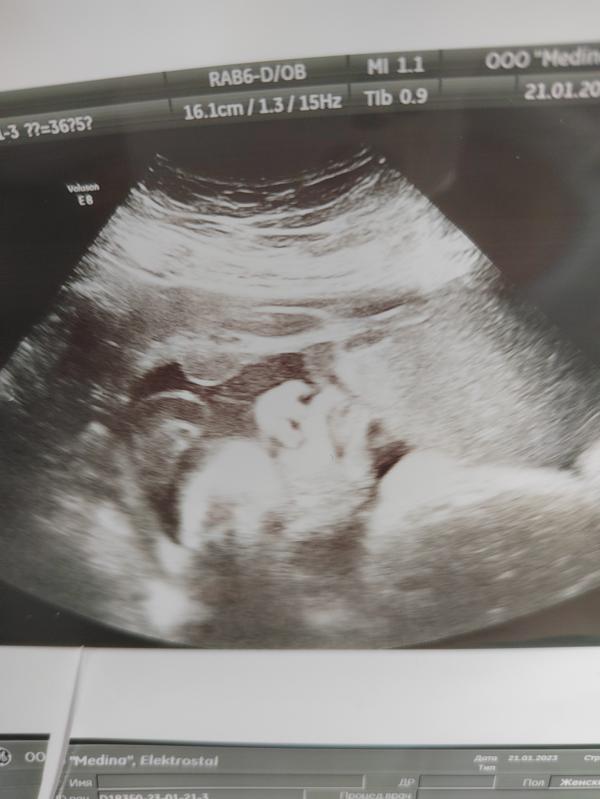

Сегодня были на контрольном УЗИ.

Итог:

-дочь головой на выход

-обвития не обнаружено

-по всем параметрам соответствует сроку (а где-то и обгоняет)

-подтвердили то, что она начала опускаться

- вес 3263+-476